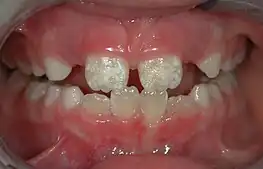

Irreversible enamel defects caused by an untreated celiac disease. They may be the only clue to its diagnosis, even in absence of gastrointestinal symptoms, but are often confused with fluorosis, tetracycline discoloration, acid reflux or other causes.[10][11][12] The National Institutes of Health include a dental exam in the diagnostic protocol of celiac disease.[10]

Dentists also encourage the prevention of oral diseases through proper hygiene and regular, twice or more yearly, checkups for professional cleaning and evaluation. Oral infections and inflammations may affect overall health and conditions in the oral cavity may be indicative of systemic diseases, such as osteoporosis, diabetes, celiac disease or cancer.[7][10][13][14] Many studies have also shown that gum disease is associated with an increased risk of diabetes, heart disease, and preterm birth. The concept that oral health can affect systemic health and disease is referred to as "oral-systemic health".